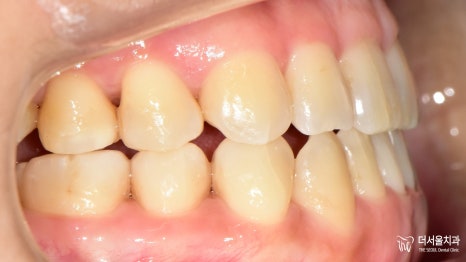

『과연 결과는 어떻게 나왔을까?』

제작된 인비절라인 과 어태치먼트의 도움을 받아

원하는 곳으로 신속하게

움직일 수 있도록 유도했습니다.

자 기나긴 교정 기간이 끝나고

드디어 마무리를 하는 날이 찾아왔습니다.

전과는 달리 제위치를 찾아간 치아들이 눈에 띕니다.

골격은 아직 Class 3급이라

완벽한 어금니 교합은 어려웠는데요.

이제는 입을 다물 때 힘을 주지 않아도

자연스럽게 다물어지기에

환자께서도 만족해하셨죠ㅎㅎ